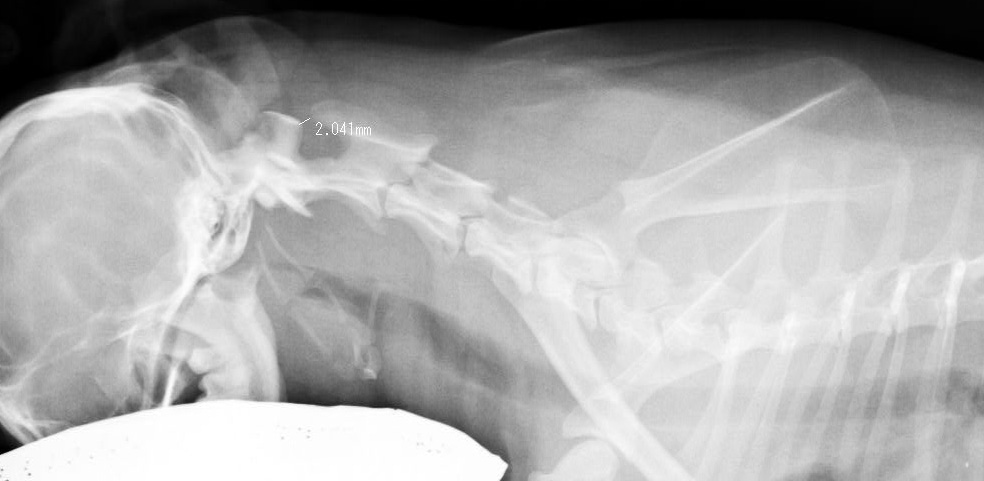

ラブラドール レトリバー 16歳 オス

左前足 肩腫れている

骨肉腫

肺に転移がみられる